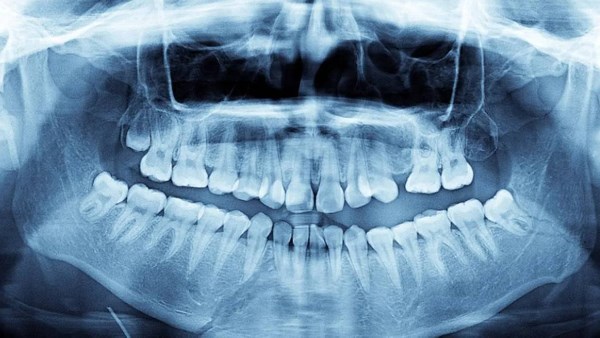

عادة ما يمتلك الإنسان البالغ 32 سناً، لكن بعض الحالات النادرة تشهد زيادة في هذا العدد دون أن يشعر أصحابها بأي مشكلة تذكر، خصوصا إذا نمت الأسنان الزائدة بشكل طبيعي.

"عندما أحصينا الأسنان اكتشفنا أن لدي 38 سناً، وبعد إجراء صور الأشعة تبين وجود أربعة أسنان أخرى لم تظهر بعد".

وبحلول أوائل عام 2023، وصل إجمالي عدد أسنانه إلى 42 سناً، معظمها نما بشكل مستقيم ومن دون أي مضاعفات صحية تُذكر.

تعرف هذه الحالة طبياً باسم فرط الأسنان، وهي ظاهرة نادرة نسبياً تصيب ما بين 0.1% و3.8% من الأشخاص حول العالم.

ويوضح أطباء الأسنان أن هذه الحالة غالبا ما تعود إلى عوامل وراثية، أو إلى خلل في ما يُعرف بـ"الصفيحة السنية"، وهي مجموعة الخلايا التي تتشكل منها الأسنان أثناء مراحل نمو الإنسان.